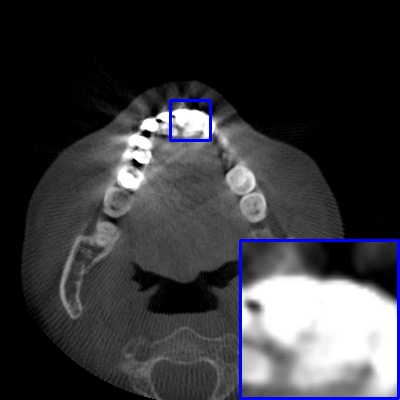

Figure 4: Comparison of MAR images by different methods on real-world MA image. The last image is the metal mask by selecting the pixel area over 2800HU in the MA image.

Results on real-world MAR. We also compare these methods on dental CBCT images with real-world metal artifacts. The visual results on one sample are shown in Fig. 4. We observe that our MARformer-T and MARformer-L well seperate the adjacent teeth and retain their shapes. This shows that our MARformers, though trained on synthetic data, are effective on real-world MAR.